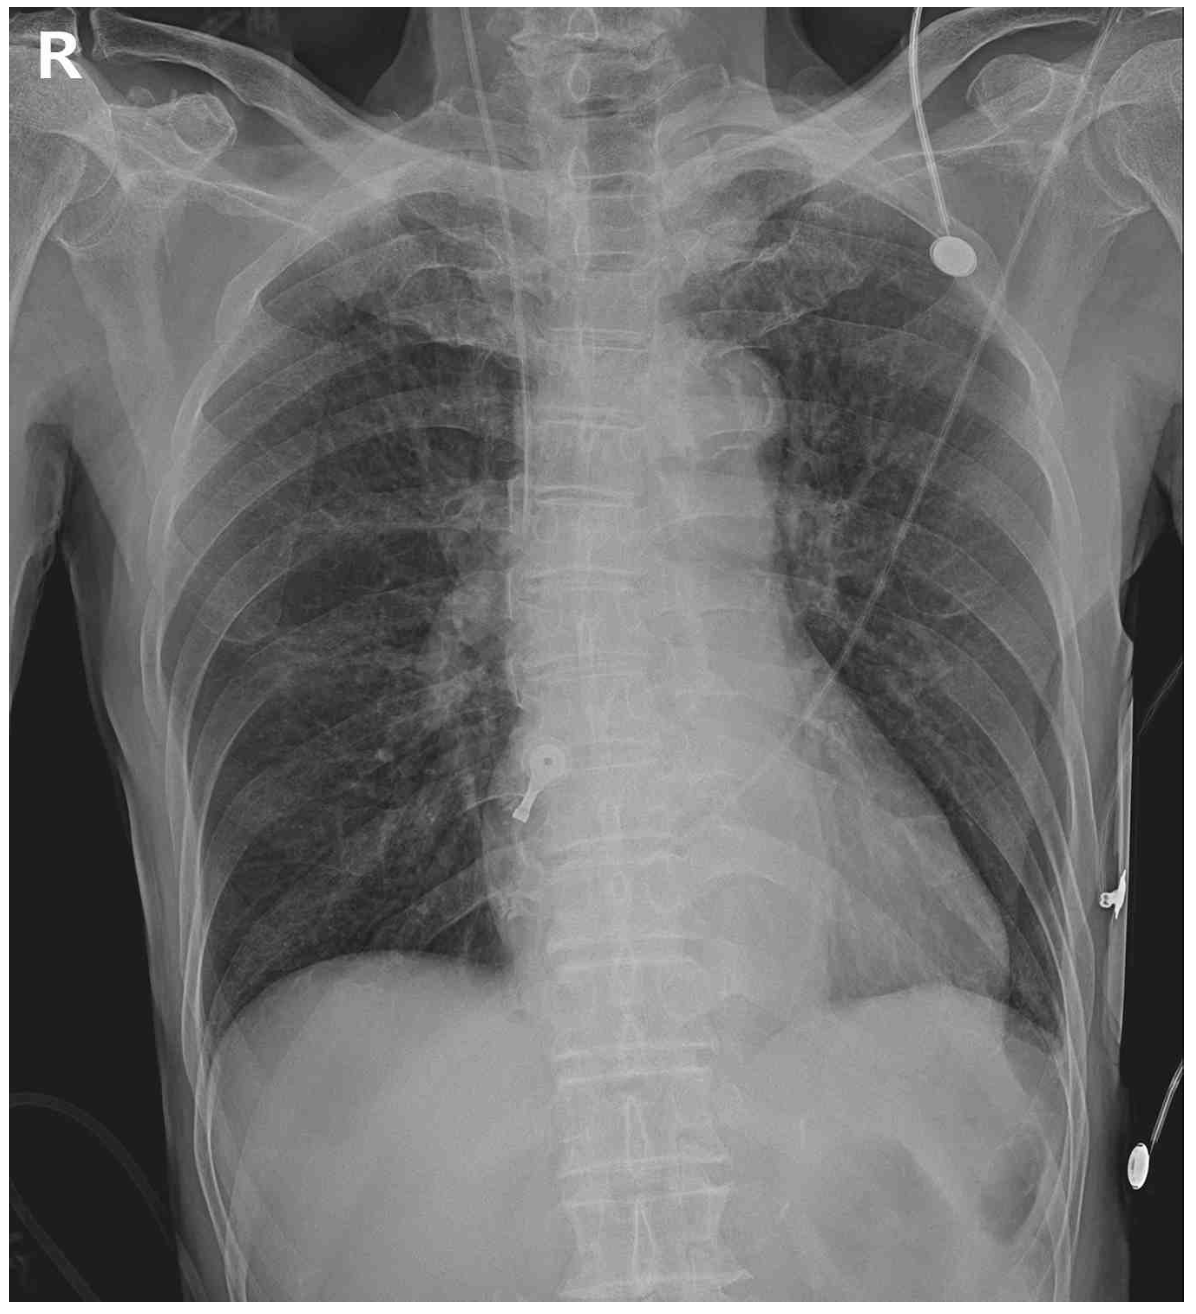

76세 남자가 1시간 전부터 가슴이 답답하고 어지럽다며 응급실에 왔다. 10년 전 급성심근경색으로 관상동맥중재술을 받고 아스피린, 스타틴, 베타차단제를 복용 중이다. 혈압 79/52 mmHg, 맥박 180회/분, 호흡 20회/분, 체온 35.4°C이다. 검사 결과는 다음과 같다. 가슴 X선사진, 응급실 도착 당시 심전도와 심장율동전환 시행 후 심전도이다. 치료는?

CXR: Cardiomegaly